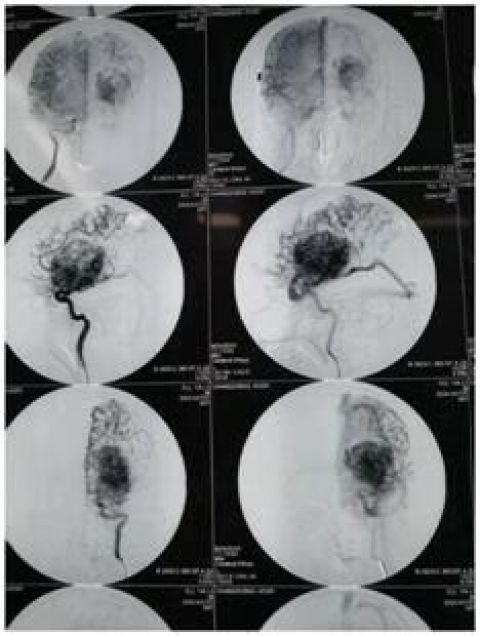

鄞州人民医院急诊科医护人员立即投入到紧张的抢救工作,神经外科主任医师高峰立即赶赴现场进行会诊。经相关检查后发现,王先生患有罕见的超巨型先天性脑动静脉畸形。该动脉畸形像一颗不定时“炸弹”,随时发生血管破裂,王先生将有生命危险。此外,王先生的畸形血管团直径达7厘米,几乎占据了一侧大脑的二分之一。

“像王先生的这种情况临床上称为巨大脑动静脉畸形,我从医近20年还是头一次遇见。”高峰仔细综合分析研究后制定了手术方案,并在征得患者家属同意下立即为王先生实施手术。

当巨大的脑血管畸形团暴露于视野时,在场的医护人员禁不住倒吸一口冷气,巨大的血管团占据了半侧大脑的二分之一。按照预定手术方案,逐一将供血动脉剥离夹闭及电凝离断,逐步沿着巨大血管团的周围分离。每分离一处血管团,都要经历一次出血、止血的考验。经过8个多小,手术终于结束了。目前,王先生已脱离生命危险,正在恢复中。